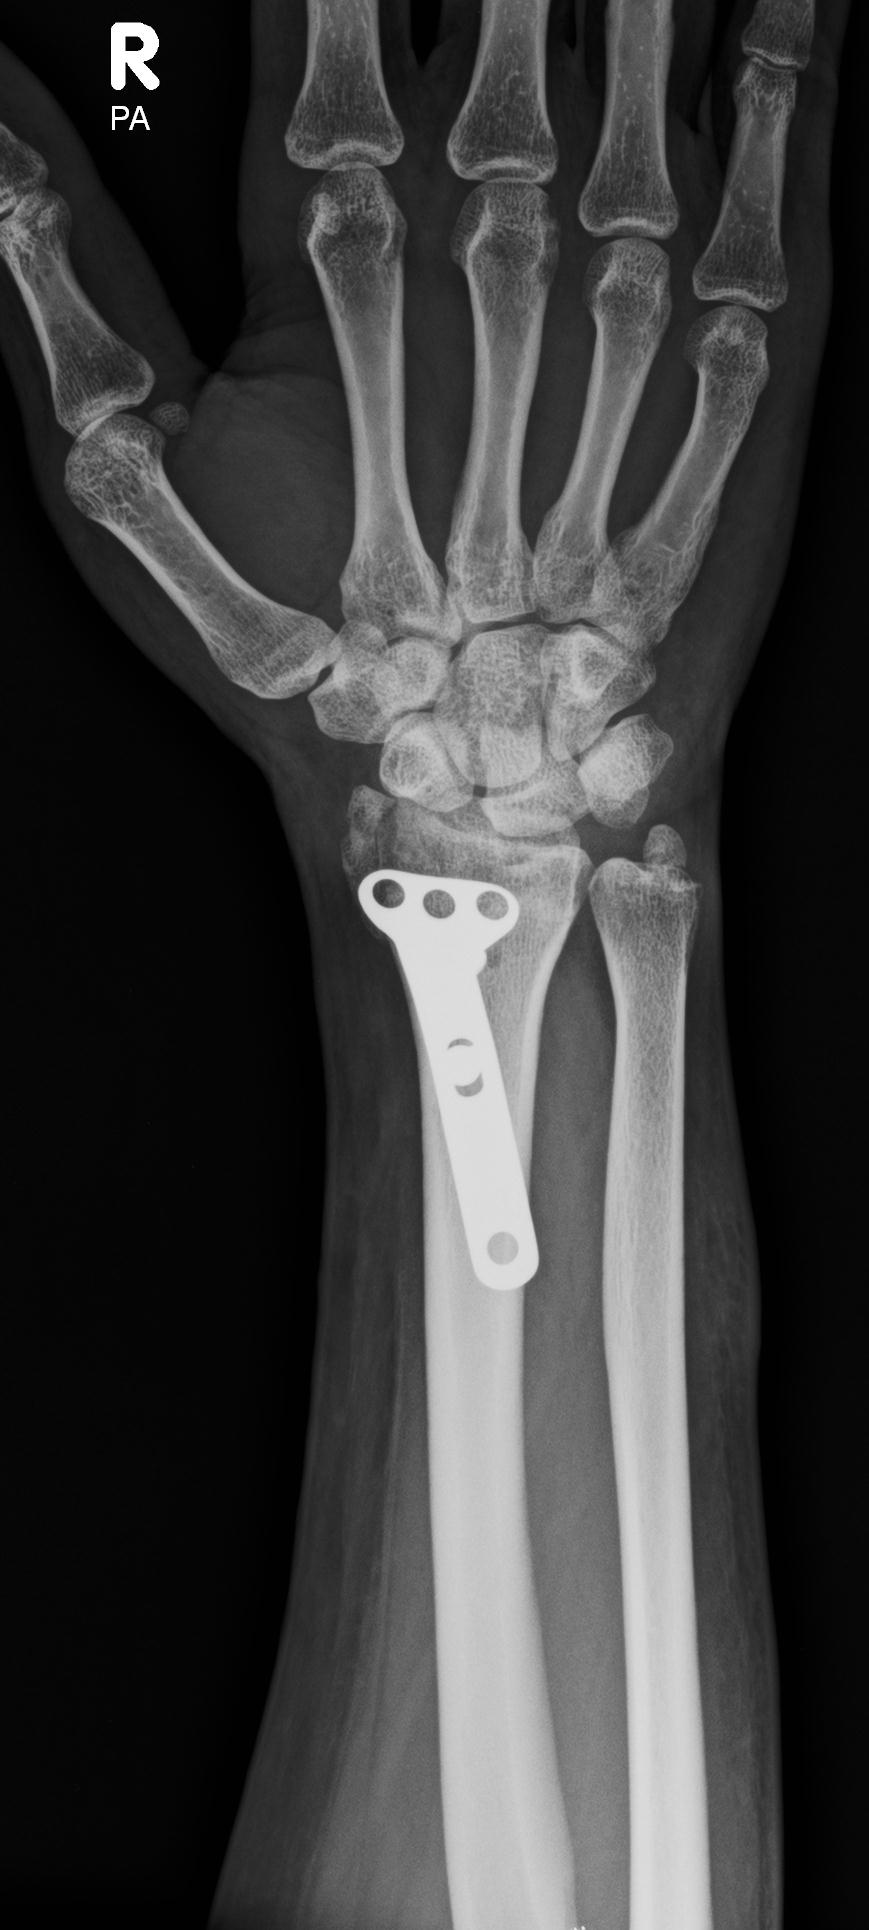

• TRAUMA

Dr Kamran Saeed is a well known and extremely experienced orthopedic and trauma surgeon of Lahore, Pakistan .